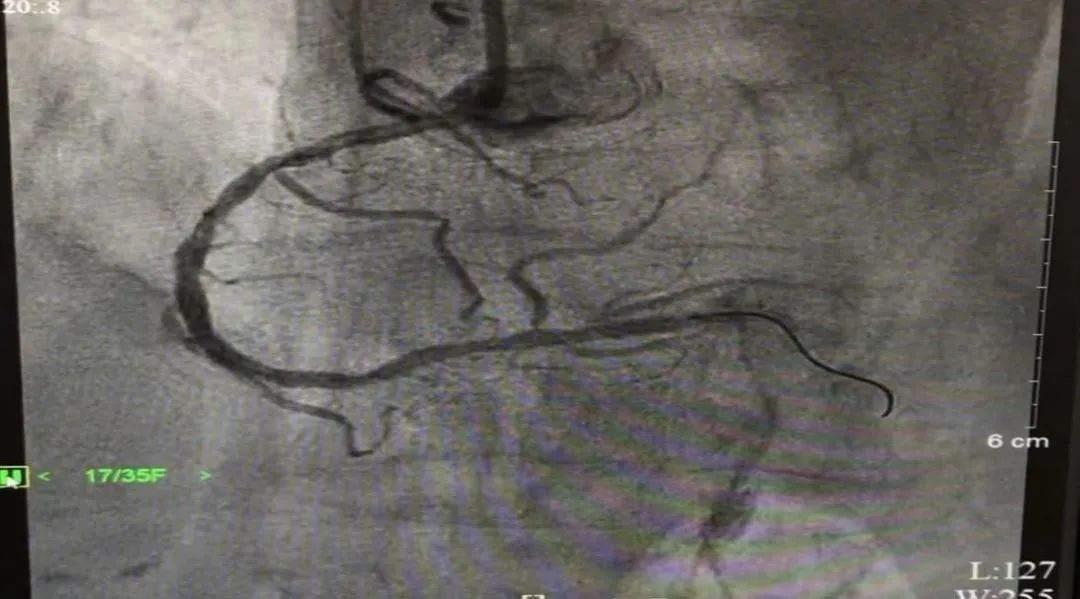

当务之急是开通罪犯血管,挽救心肌细胞,保护心功能。对比心电图及造影结果,介入团队进行快速研究后,立即着手处理罪犯血管--右冠脉。黎国德与心血管内科二区陈明主治医师配合默契,仅用29分钟便在后降支近段及右冠脉中段各植入冠状动脉支架1枚。

▲术后造影图像:右冠脉中段及后降支狭窄消失,供血明显改善